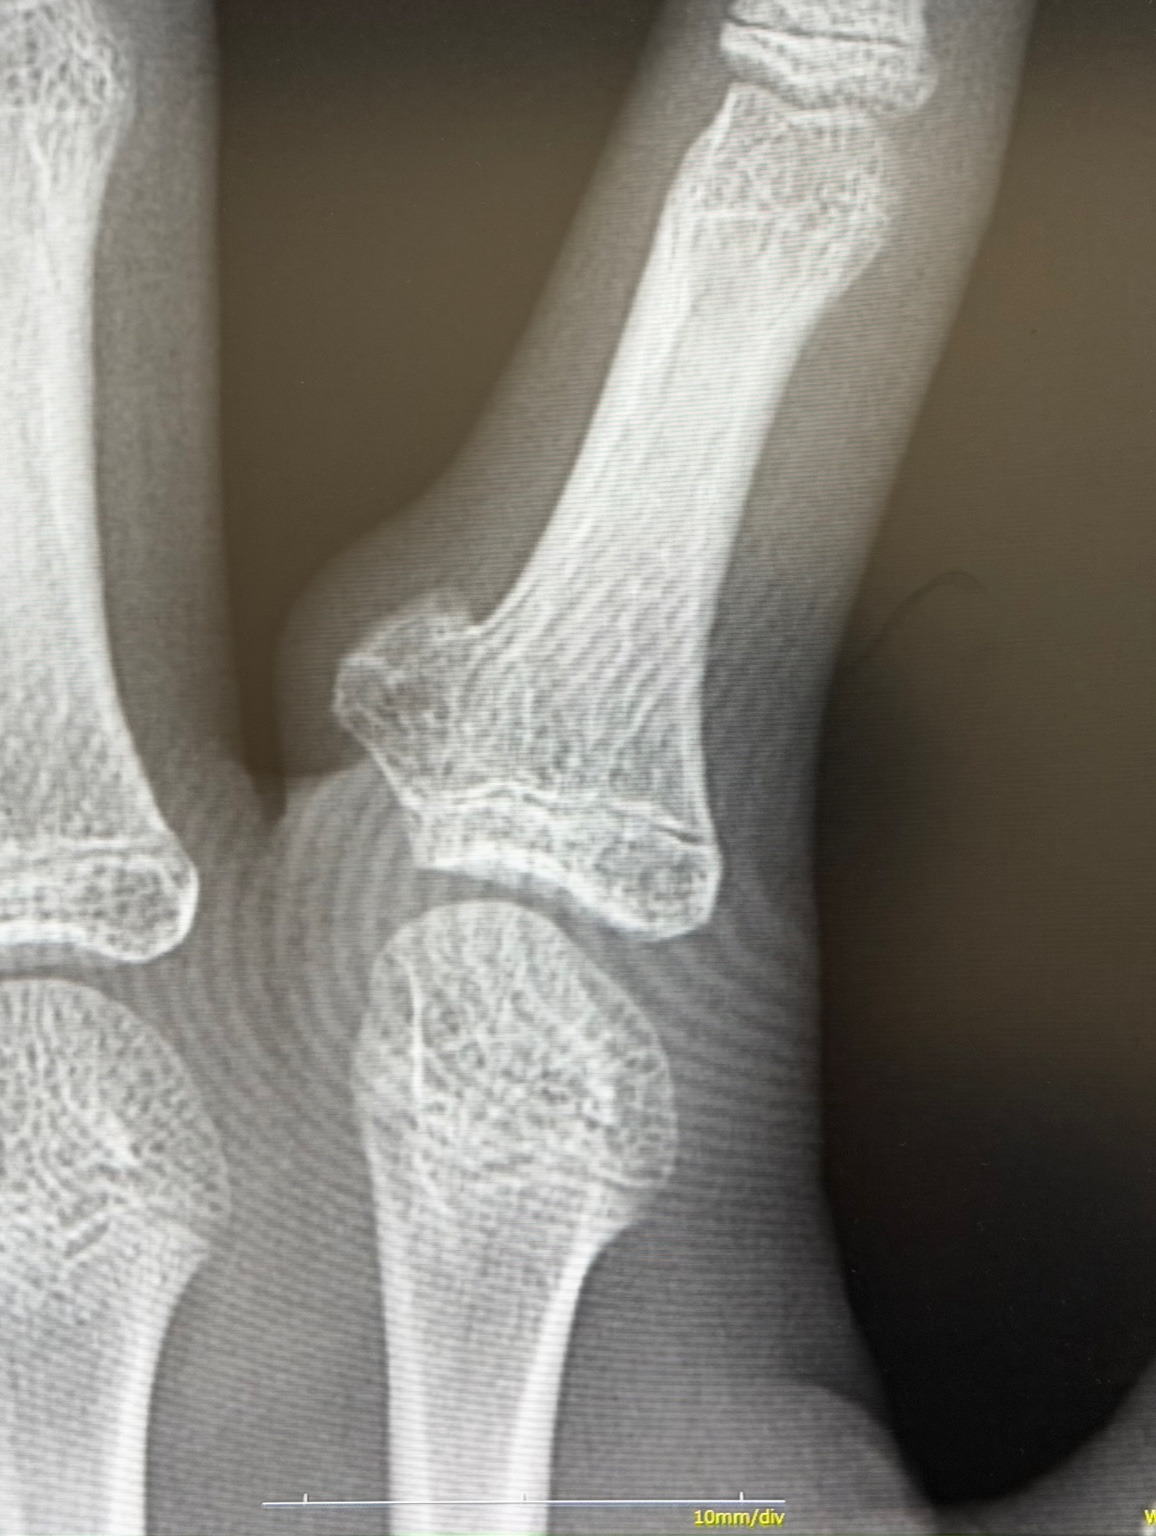

画像診断では単純X線がまず有用で、皮質骨から連続して茸状あるいは台地状に隆起する骨性隆起として描出されます(下の画像参照:患者さまより許可を得て掲載)。

CTやMRIでは、基部における皮質骨・骨髄との連続性の確認や軟骨帽の厚み評価、周囲神経や血管への影響評価、脊柱管内進展の有無の把握に役立ちます。鑑別診断として傍骨性骨肉腫が重要で、骨軟骨腫が皮質骨・骨髄との明確な連続性を示すのに対し、傍骨性骨肉腫ではこの連続性がみられない点が決め手となりますが、両者は画像上きわめて類似することがあるため注意が必要です。